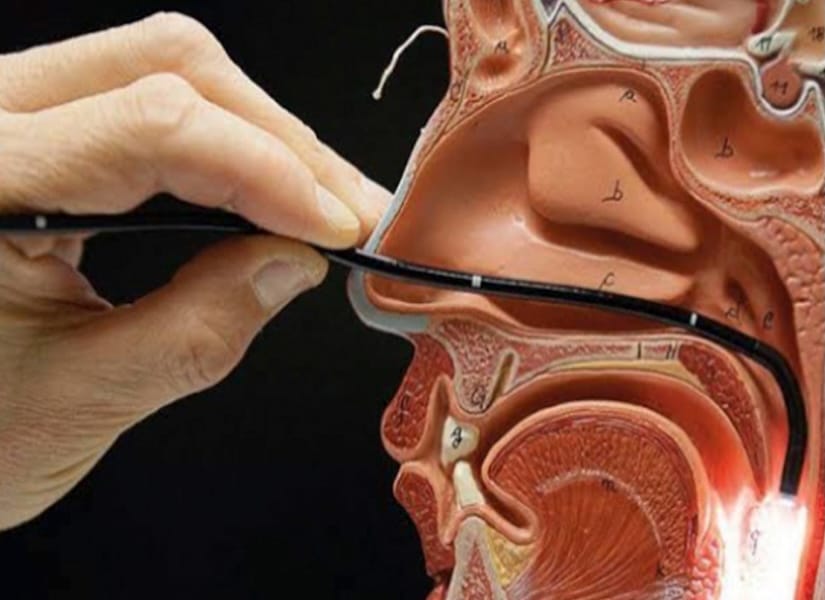

- Diagnóstico y tratamiento de rinitis, sinusitis y desviación del tabique nasal

- Atención de trastornos de la voz y cuerdas vocales

- Tecnología médica avanzada en diagnóstico y tratamiento.